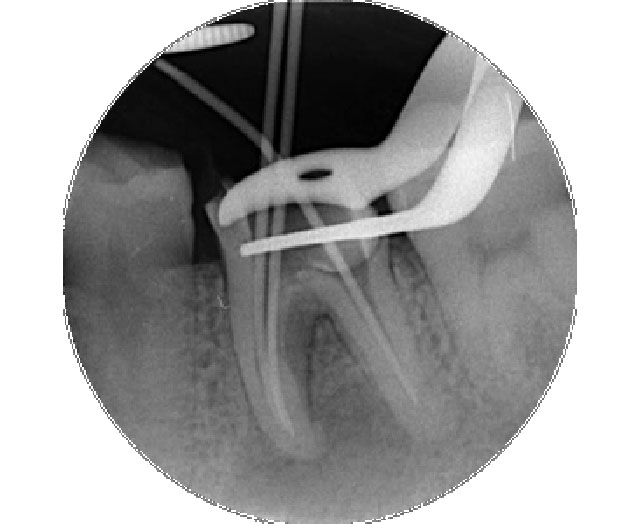

1.虫歯と神経を取って、清掃と消毒を行います

• ほとんどの場合、麻酔が必要です。

• それまで痛みがなかった歯でも、神経を取った後は数日間痛むことがあります。

• 通常、1回では終わりません。

感染源を完全に取り除き清掃・消毒するのに回数がかかる場合があります。

2.神経を取った後の空洞に詰め物をします

• 感染がないことが確認できて、痛みが落ち着いたら、仕上げの詰め物です。